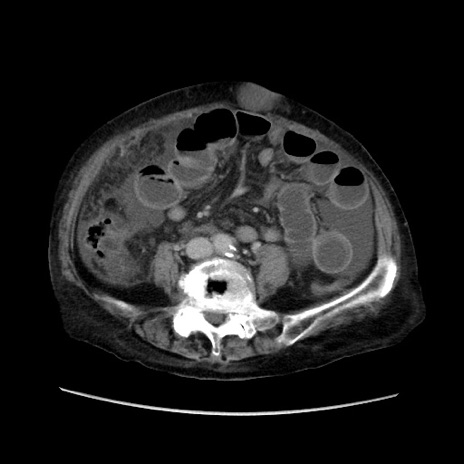

矢状断像

【症例】80歳代 女性

【主訴】腹部膨満感

【現病歴】他院にて肝硬変にてフォロー中。1週間前から便秘、腹部膨満感、臍部腫瘤あり受診となる。

【既往歴】肝硬変

【身体所見】腹部膨隆あり、皮膚変化なし、疼痛なし。

【データ】WBC 4600、CRP 0.25